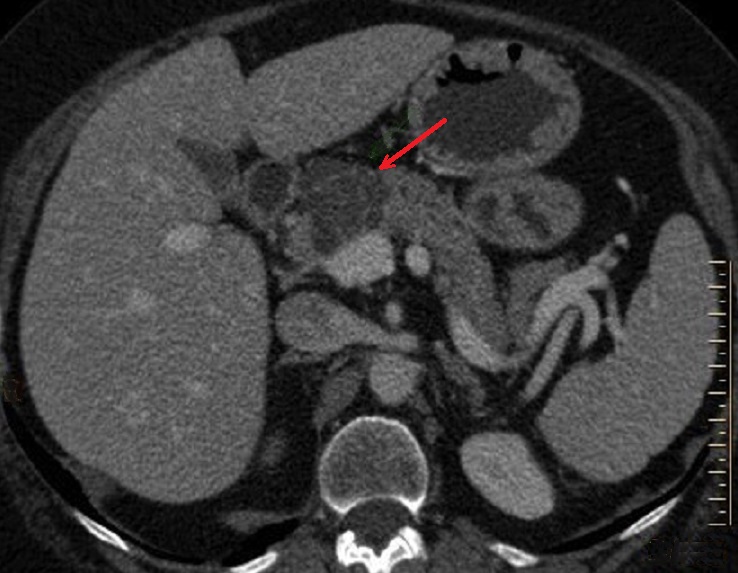

Un grand cystadenome de la tete du pancreas a

aspect hypodense multikystique polylobulaire a

cicatrice et calcification centrale ( fleche rouge )

. Tomodensitographie en coupe axiale |

Une autre cas cystadenome sereux

multikystique au queue du panceras avec image

calcification central ( fleche rouge ) |